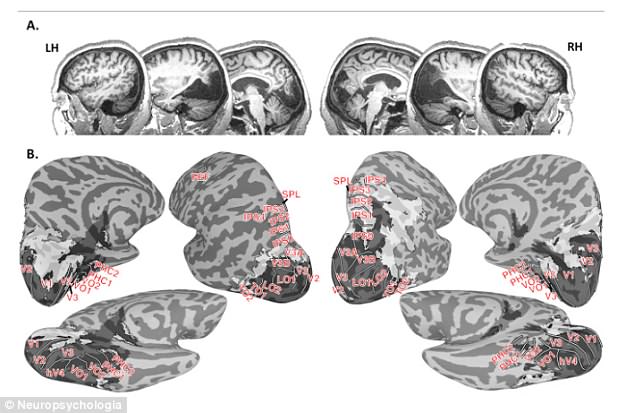

Ảnh scan não cho thấy bà Canning bị thiếu một mẩu mô não có kích thước bằng quả táo ở phía sau não. Ảnh trên tạp chí Neuropscyhologia

Nói về nghiên cứu của mình, Giáo sư Culham cho biết: “Đây là công trình nghiên cứu có lẽ giàu đặc tính nhất từng được tiến hành trên hệ thống thị giác của một bệnh nhân. Bệnh nhân bị thiếu một mẩu mô não có kích thước bằng quả táo ở phía sau não - gần như toàn bộ thùy chẩm, nơi xử lý thị lực“.